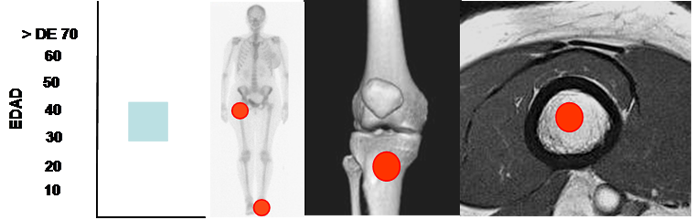

Fig 167. Lipoma intraoseo.

Mayor frecuencia entre la 4º y 5º década. Predominio en huesos largos y el calcáneo.

Lesión metafisiaria, de ubicación central.